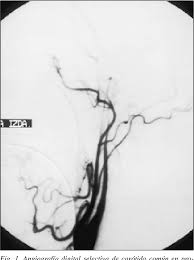

Consenso Latinoamericano Sobre El Uso Del Doppler Transcraneal En El Diagnostico De Muerte Encefalica

Consenso Latinoamericano Sobre El Uso Del Doppler Transcraneal En El Diagnostico De Muerte Encefalica from www.scielo.br